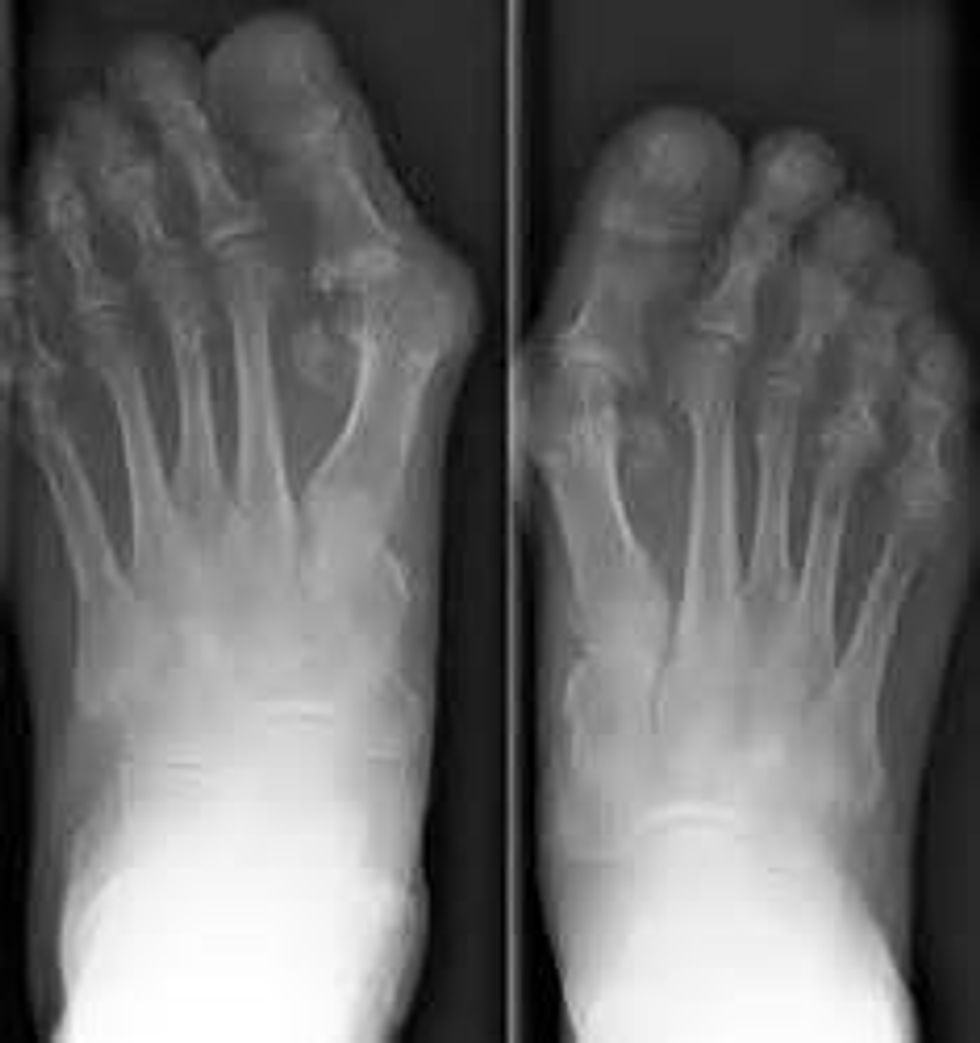

I was diagnosed with Juvenile Rheumatoid Arthritis. Rheumatoid Arthritis is not like typical osteoarthritis, which just is bone pain, it is much more. Rheumatoid Arthritis causes severe joint pain, autoimmune issues, skin rashes and also makes you very weak and tired. I couldn't jump, run, lift weights, all I could do was sleep. I became depressed, and let anxiety take over my life.